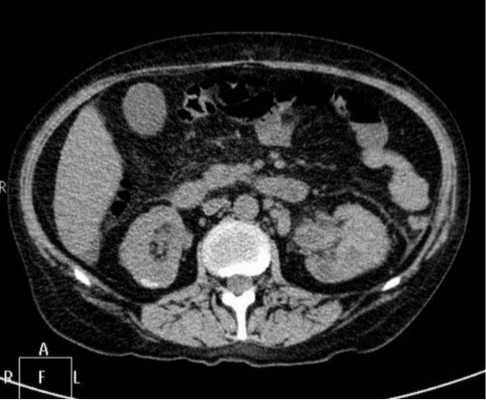

Снимок КТ почек

Обычный рентгеновский снимок не позволяет визуально отличить мышечную и жировую ткань, на нем видны только кости и другие твердые структуры. Компьютерная томограмма, благодаря специальной обработке, позволяет дифференцировать плотность всех органов, попавших на снимок.

На КТ мочевыделительной системы оценивают состояние сразу нескольких органов:

почек: паренхимы и чашечно-лоханочной системы;

сосудов почечной ножки;

регионарных лимфатических узлов.

Помимо самой мочевыделительной системы, на томограмме определяются поясничные

позвонки, петли кишечника. Компьютерная томография позволяет оценить размеры органов, их расположение, наличие травм, опухолей, камней. Воспаление определяют по косвенным признакам и однозначно утверждать о его наличии можно только после сдачи анализа мочи, прохождения ультразвукового исследования органов забрюшинного пространства.